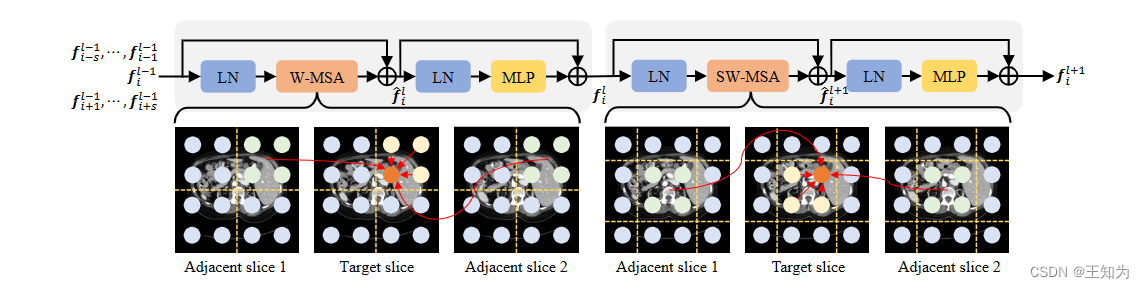

图3. IF-Swin transformer模块的示意图。它包含两个连续的IF-Swin transformer,具有不同的窗口划分配置。基于窗口的自注意力扩展到切片间的维度,促使目标切片像素学习切片内和切片间的上下文。